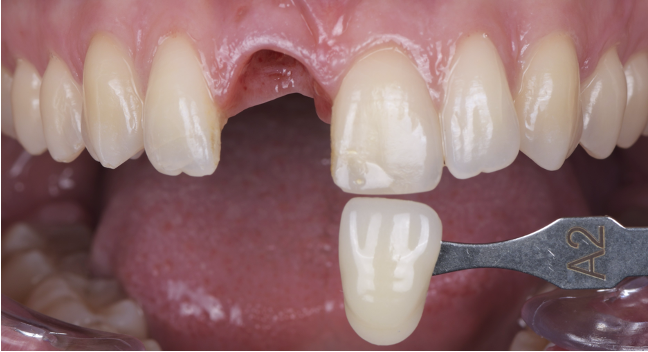

Ces empreintes sont alors transmises au laboratoire (Laboratoire Dominique Watzki). La teinte est relevée grâce à un teintier Vita classique et grâce également à l’Optishade et transmise au laboratoire.

La patiente revient pour la pose de la prothèse d’usage. Nous réalisons donc un essayage de cette prothèse d’usage avant de réaliser le composite sur la dent 21.